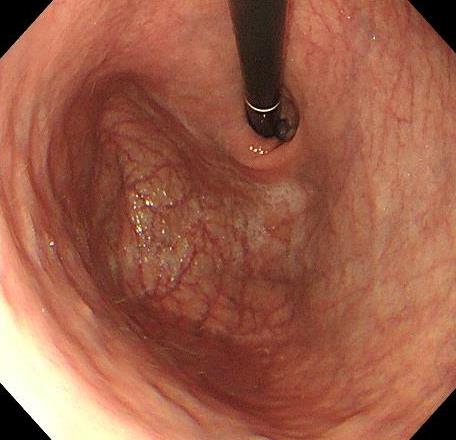

摘要:目的 探讨利那洛肽联合西甲硅油与复方聚乙二醇电解质散(PEG)对便秘患者肠道清洁效果的有效性和安全性。方法 采用前瞻性随机对照试验,通过单盲法,纳入2023年4月-2024年8月于该院消化内镜中心行结肠镜检查的便秘患者383例,随机分为常规组(128例)、实验A组(128例)和实验B组(127例)。常规组采用3 L PEG(Ⅰ)溶液,实验A组采用290 μg利那洛肽 + 2 L PEG溶液,实验B组采用290 μg利那洛肽 + 30 mL西甲硅油+2 L PEG溶液。比较3组患者的肠道准备效果[Boston肠道准备量表(BBPS)评分和去泡效果]、病变检出率、首次排便间隔时间、排便次数、盲肠插管成功率、进镜时间、退镜时间、不良反应发生率和重复检查意愿等。结果 3组患者BBPS评分比较,差异无统计学意义(P > 0.05);实验B组的去泡效果评分明显低于常规组和实验A组,差异均有统计学意义(P < 0.05);实验B组的病变总检出率和息肉检出率明显高于常规组和实验A组,差异均有统计学意义(P < 0.05);常规组的首次排便间隔时间明显长于实验A组和实验B组,差异均有统计学意义(P < 0.05);3组患者排便次数比较,差异无统计学意义(P > 0.05);3组患者盲肠插管成功率均为100.0%,进镜时间相当,差异均无统计学意义(P > 0.05);实验B组的退镜时间明显短于常规组和实验A组,差异均有统计学意义(P < 0.05);常规组腹胀腹痛发生率和不良反应总发生率明显高于实验A组和实验B组,差异均有统计学意义(P < 0.05);常规组重复检查意愿率明显低于实验A组和实验B组,差异均有统计学意义(P < 0.05)。结论 290 μg利那洛肽联合30 mL西甲硅油与2 L PEG溶液方案在便秘患者肠道准备上具有优势,较3 L PEG溶液和290 μg利那洛肽+2 L PEG溶液方案,可获得更好的肠道清洁效果,且安全性和患者重复检查意愿率高,可作为便秘患者肠道准备的推荐方案。